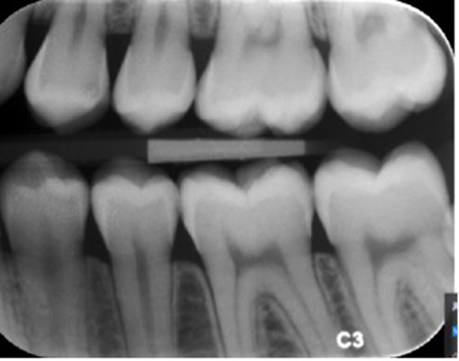

Er denne optagelse ortoradial? Begrund dit svar.

approksimalrum ses åbne

ingen overlap af kontaktpunkter

emaljekonturer kan følges mesialt og distalt

tandkroner fremstår adskilt

ingen tegn på horisontal vinklingsfejl